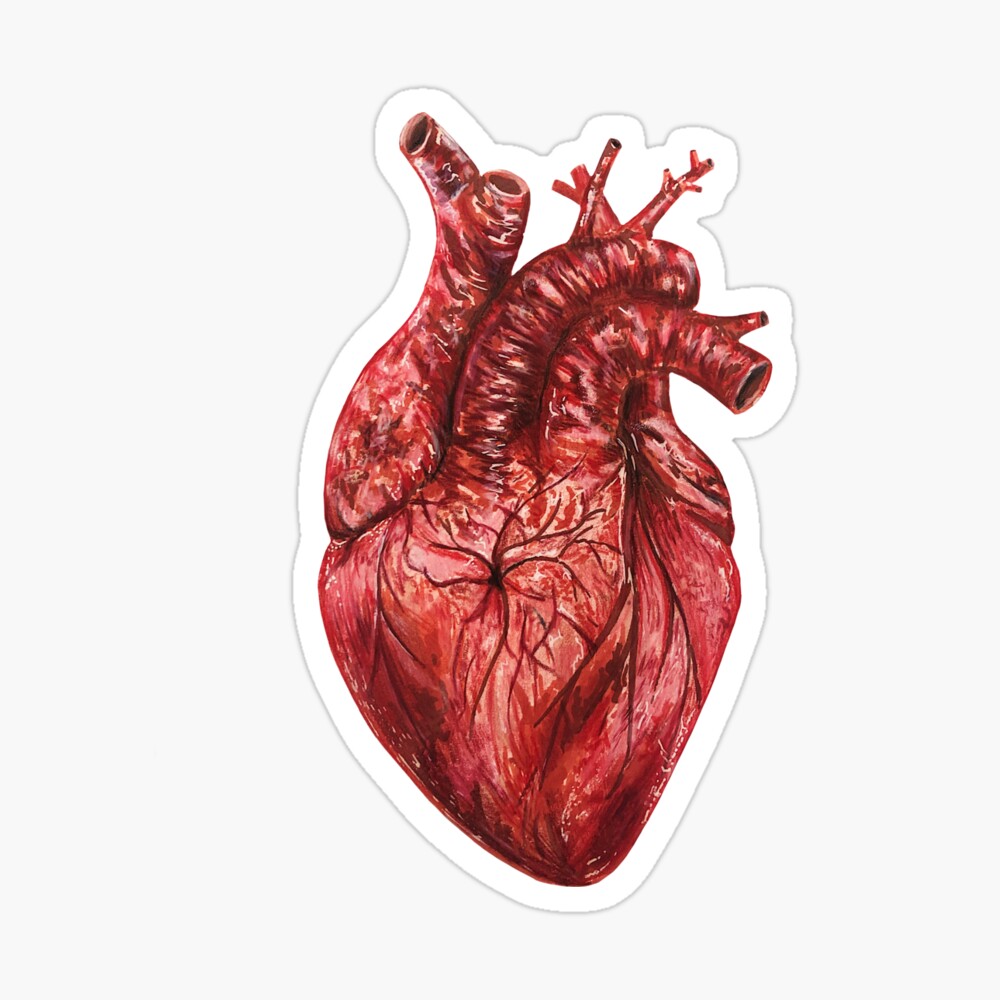

Анатомия желудка и сердца: визуализация и изучение